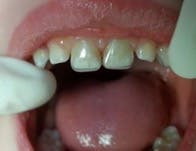

Leigh was three-years-old when he first came to my office with failed restorations and rampant caries (figure 1). He had come from overseas where both he and his mother had bad experiences with dentists and developed severe dental phobia. His mother was delighted to see that her children did not scream during treatment in our office.

Figure 1: Child presents with failed composite restorations and rampant caries.